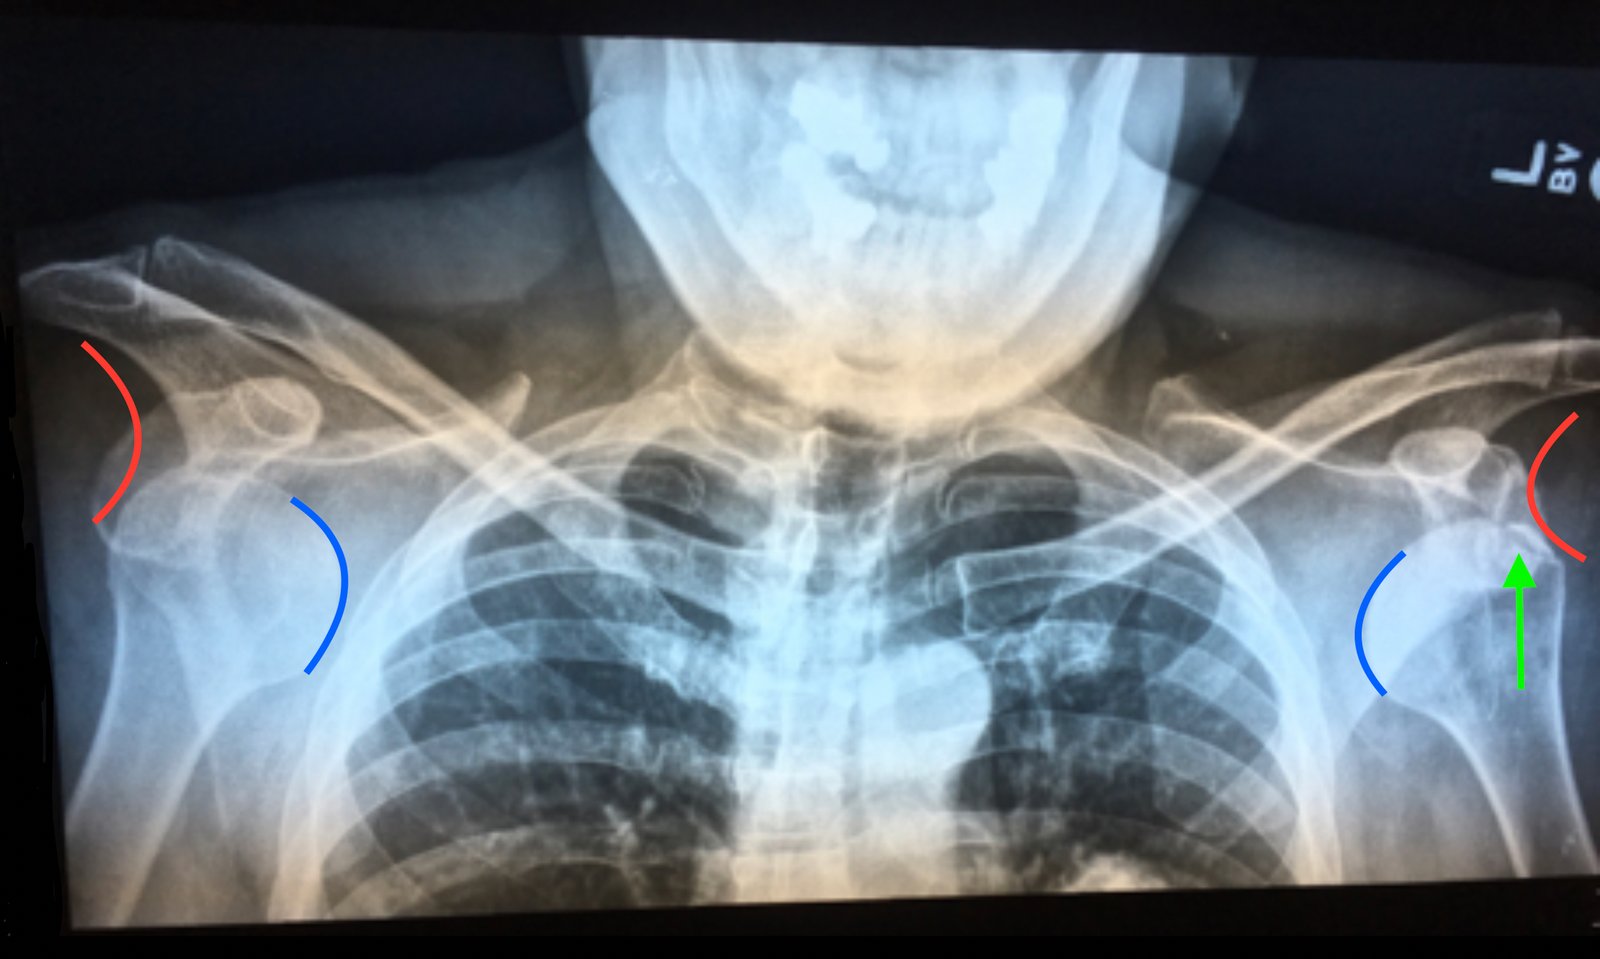

The patient was a 60-year-old male who had been skiing when he abruptly fell with arms overhead (superman position). The patient immediately experienced bilateral shoulder pain and was rushed to the clinic associated with the ski resort. On physical exam, he had bilateral step-off deformities and both shoulders were abducted approximately 15 degrees with elbows flexed at 90 degrees. He promptly received X-rays which demonstrated bilateral anterior shoulder dislocation and left humeral head fracture.

An anteroposterior chest X-ray demonstrates bilateral shoulder dislocations. Both the right and left humeral heads (blue lines) are displaced medially, anteriorly, and inferiorly from their normal positions in the glenoid fossae (red lines), thus signifying bilateral anterior dislocations. There is also a fracture of the left humeral head at the greater tubercle (green arrow).